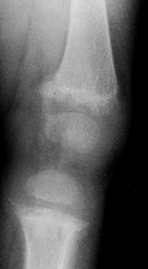

The metaphyses are flared or cupped. The long bones may be abnormally

bowed because they are unable to withstand mechanical stress. The

trabecular pattern of the bone is indistinct. Osteopenia is present.

Looser’s lines (radiolucent lines extending transversely across the

axis of the bone) are associated with rickets and are present in

approximately 20% of patients with all forms of rickets (223).

![]() |

|

Figure 180.26. Osteopenia and growth plate widening in the knee of a 1-year-old girl with nutritional rickets.